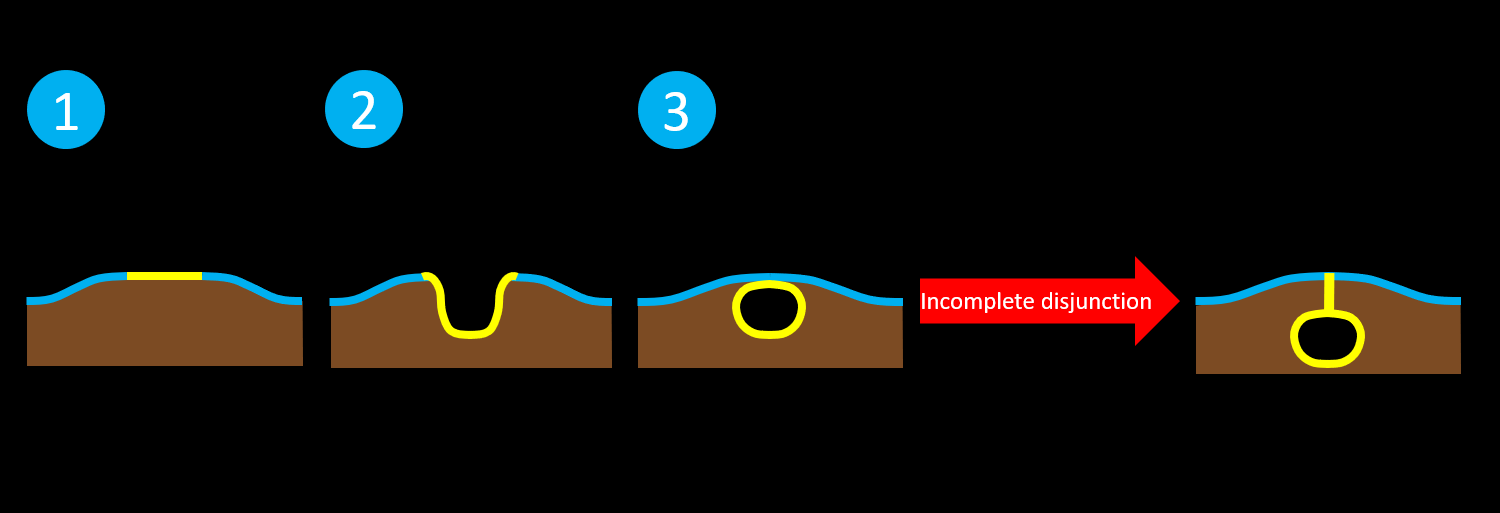

- Incomplete disjunction results in a closed neural tube defect with a persistent dermal sinus attached to the neural tube

- May have associated intradural dermoid or epidermoid lesions

- Incomplete disjunction results in a closed neural tube defect with a persistent dermal sinus attached to the neural tube

-

-

-